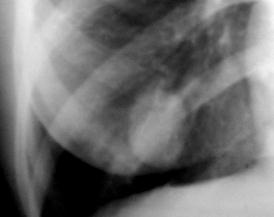

Рис. 12. Ограниченное затемнение левого легочного поля (

экссудативный плеврит

)